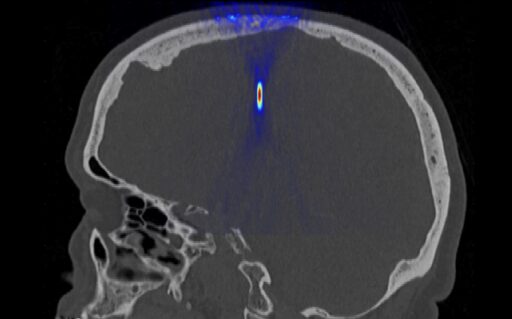

Ultrasound for non-invasive neurosurgery

Development of non-invasive treatment modalities for brain tumors and neurodegenerative diseases

Ultrasonic methods in diagnostics and therapy of the brain

Aberration correction, expansion of available brain area, ultrasound brain diagnostics